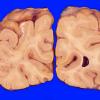

VASCULAR

Small Vessel Disease (3)